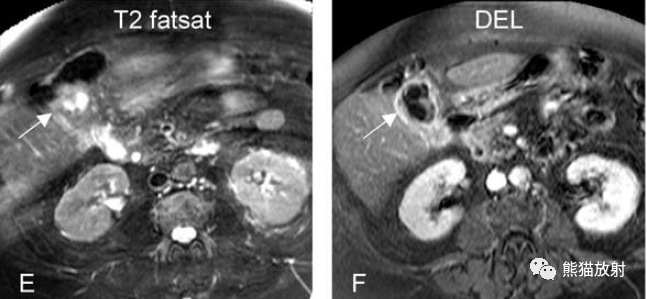

膽囊癌。A~D圖:上方層面,表現如上所述,形成腫物侵及肝臟。E、F圖:下方層面示膽囊壁不規則增厚,明顯不均質強化。

另一例膽囊癌,T2WI及增強延遲期顯示膽囊壁不均勻增厚并明顯強化。